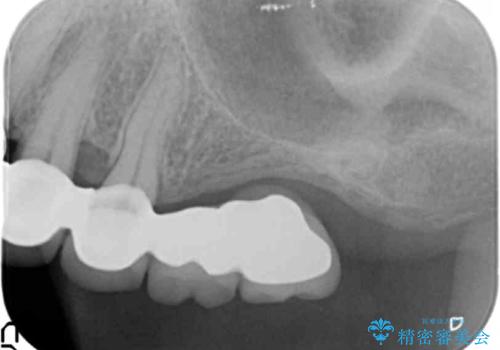

- 他院で治療した左上のセラミック部位の痛みを訴えて来院されました。

支台となる小臼歯に過大な負担のかかる遊離端ブリッジが装着されていたため、義歯かインプラントを用いた再補綴計画を提案しよりしっかりと噛めるインプラント治療をご希望されました。

親知らずを除く、一番後ろの歯を失った場合(第二大臼歯)ブリッジによる機能回復は支台となる歯の大きな負担となり将来的に歯をさらに失う原因の一つとなりえます。

力学的に無理のある遊離端ブリッジをインプラントを用いて長期的な予後を見込める補綴状態へと改善しました。